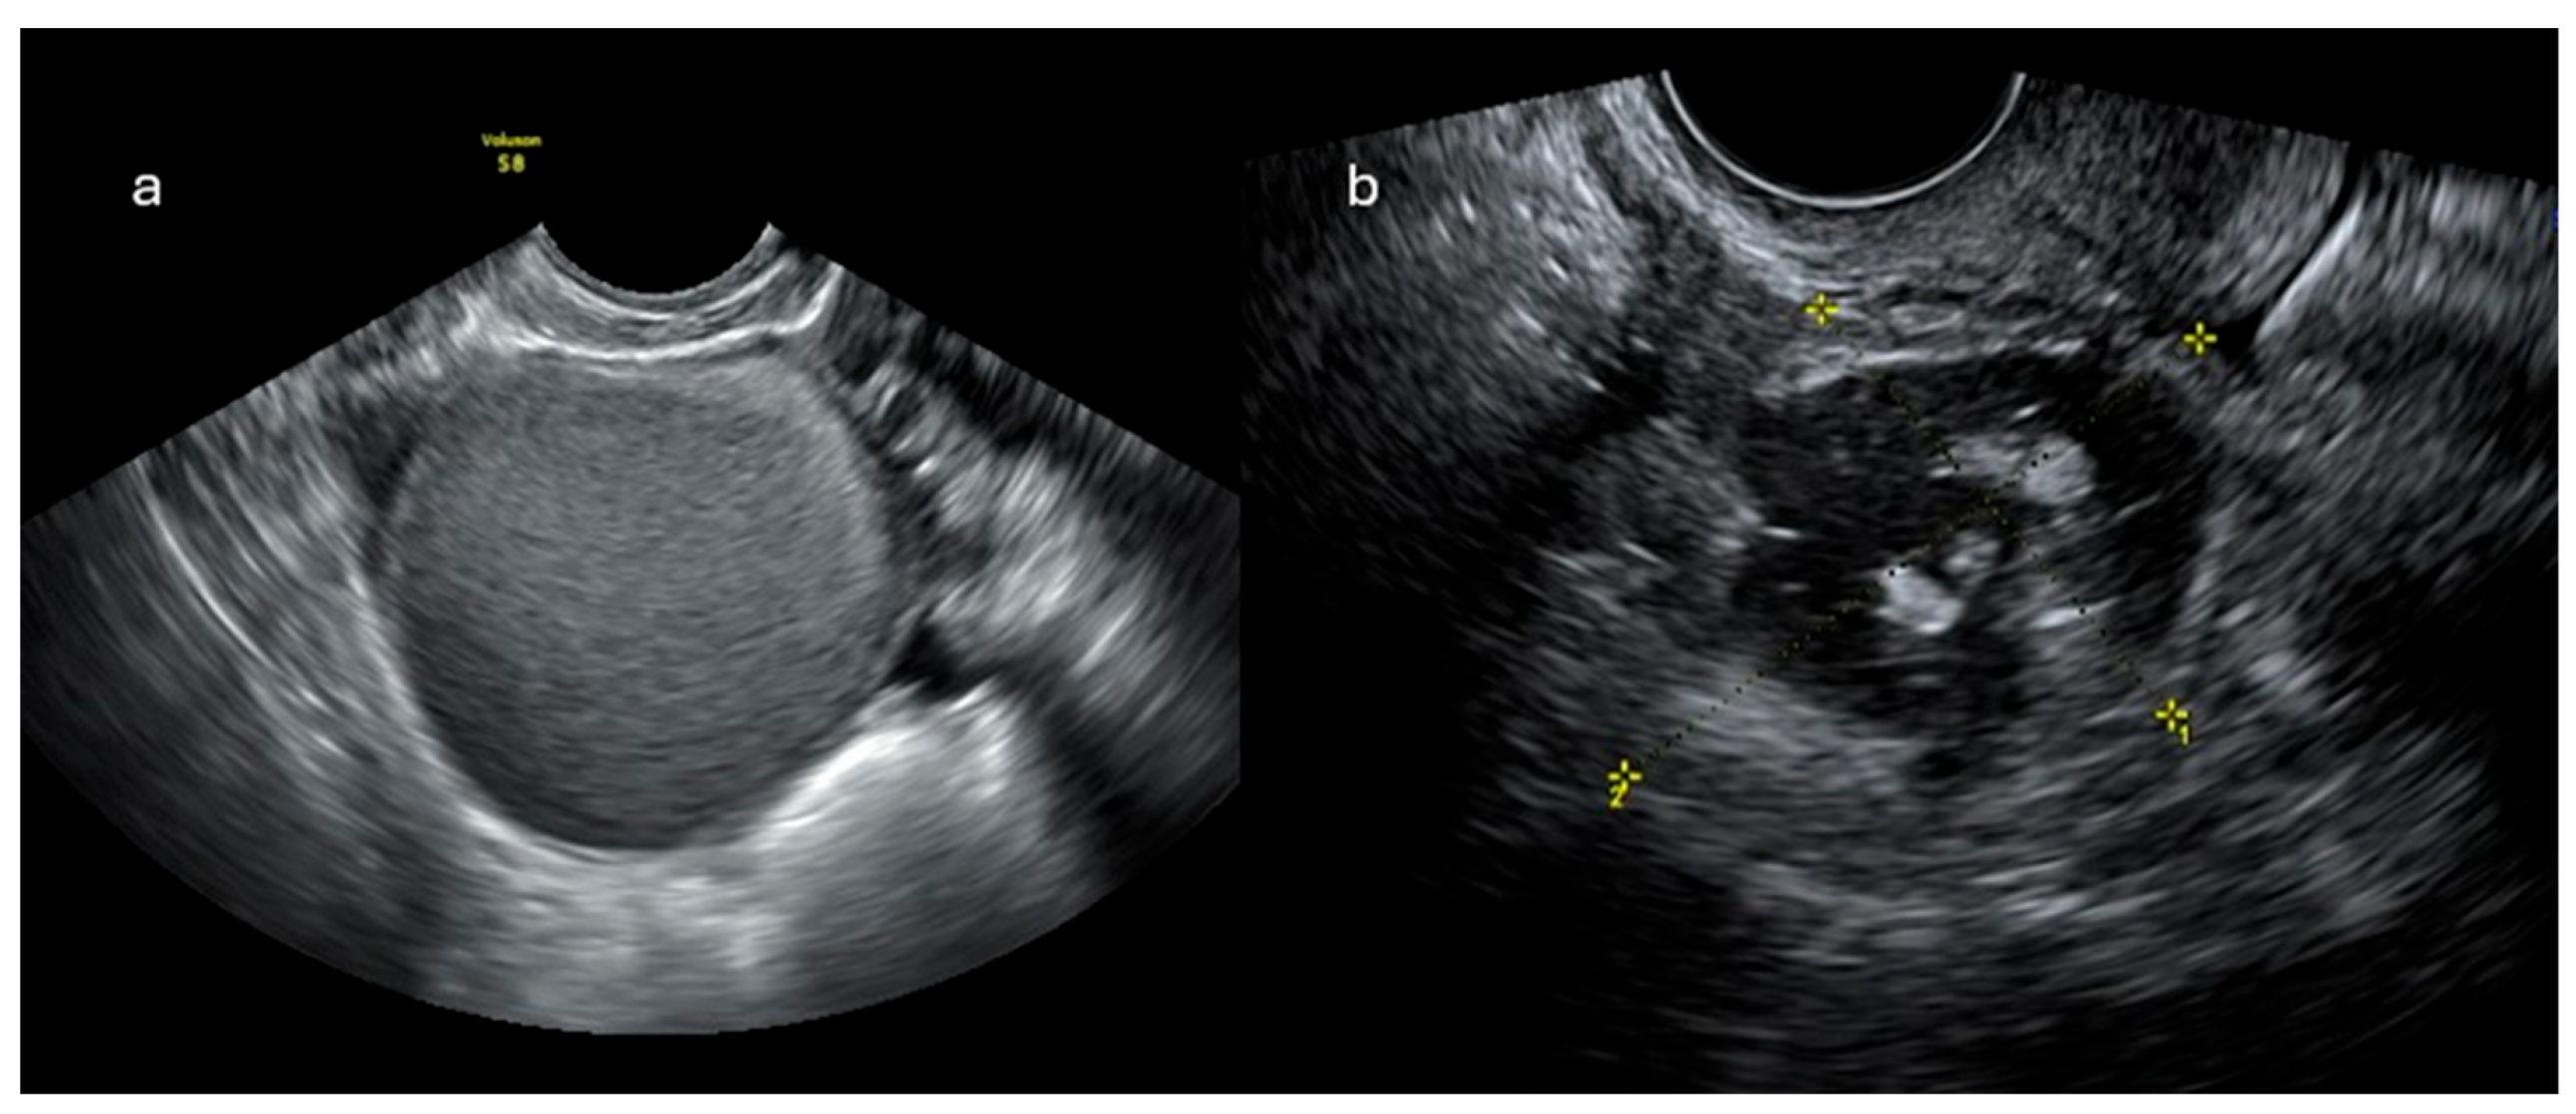

2.1. Ultrasonographic Imaging

2.1.2. O-RADS US

- O-RADS 0: incomplete evaluation

- O-RADS 1: physiological findings

- O-RADS 2: lesions almost certainly benign (<1% risk of malignancy)

- O-RADS 3: lesions with low risk of malignancy (1-10%)

- O-RADS 4: lesions with intermediate risk of malignancy (10-50%)

- O-RADS 5: lesions with high risk of malignancy (>50%)